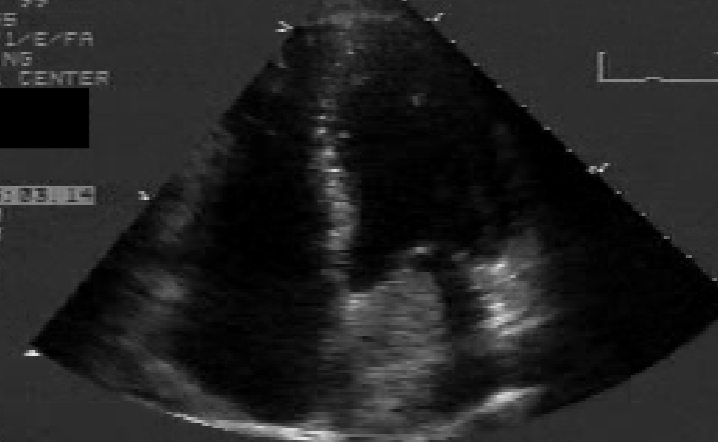

Classic LA Myxoma

echogenic mass located in the body of the LA in systole and prolapses through the mitral orifice in diastole

causes stenosis if large enough

narrowing of orifice

mimics MS

Myxoma 2D findings:

visualization of myxoma

allows detection, location, + sizing

exaggerated motion of myxoma

d/t prolapsing from LA into the LV